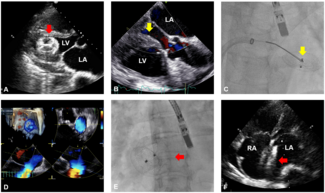

A 76-year-old woman with atrial septal defect (ASD) had previously undergone occluder implantation at another institution. At that time, preoperative transesophageal echocardiography revealed an ASD with deficient retro-aortic rim.